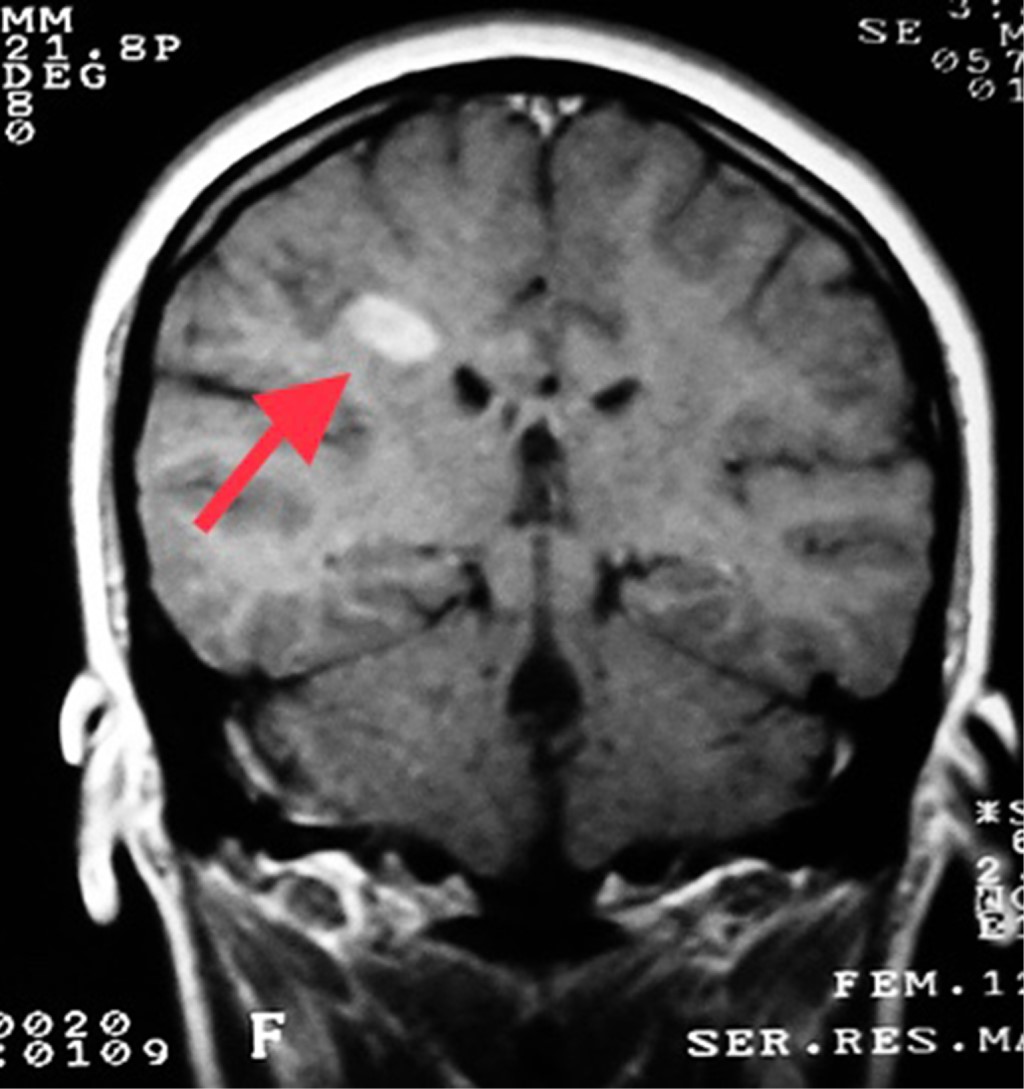

Objective: We describe two adolescent patients with multiple sclerosis, which is a demyelinating disease of the central nervous system. Presentation of the cases: The first case was a 14-year-old female patient with overweight; her condition was characterized by dizziness, headache, paresthesia in the lower limbs, diplopia and bradylalia. On physical examination, compatible data of cerebellar involvement were identified. A magnetic resonance imaging (MRI) of the skull showed areas of demyelination in the posterior fossa. Multiple sclerosis, the relapsing-remitting variety, is diagnosed. After the administration of steroids and beta interferon, there was improvement in symptoms. Second case: 13-year-old female, who presented fall from her own height, bladder incontinence, loss of strength in the left arm and leg. On physical examination, left hemiparesis was detected. MRI: demyelination data in lateral ventricle, cerebellum and spinal cord. The patient improved after starting steroids and interferon. Conclusions: The clinical presentation of multiple sclerosis in pediatric patients is a challenge, since it is a condition with unspecific manifestations. Establishing the diagnosis requires multiple studies. The earlier treatment is started, the more favorable the prognosis.

Figure 1